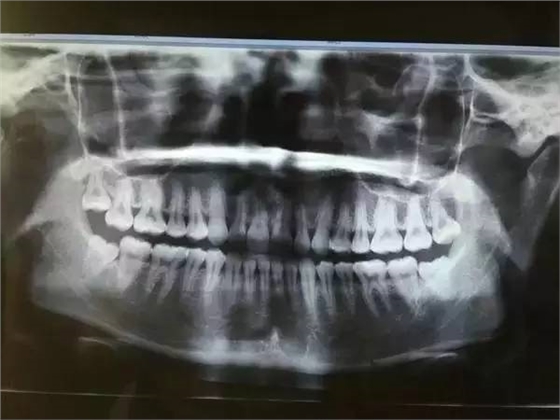

一般患者不自知,而由牙醫(yī)以X光確診得知。一般智齒萌生的空間缺乏,而會倒在第二大臼齒上,因而形成第二大臼齒清洗不易,乃至是牙齒部分吸收的表象,形成患者不舒服或牙疼。

6、阻生齒

一般這是最討厭的一種,牙醫(yī)會覺得很難搞定,但患者卻不一定有感受,因而忽略了。這一種類型的牙齒,一般埋在齒槽骨的里邊,假如會痛,或是確診會有病灶發(fā)作的時分,就需求拔除了。